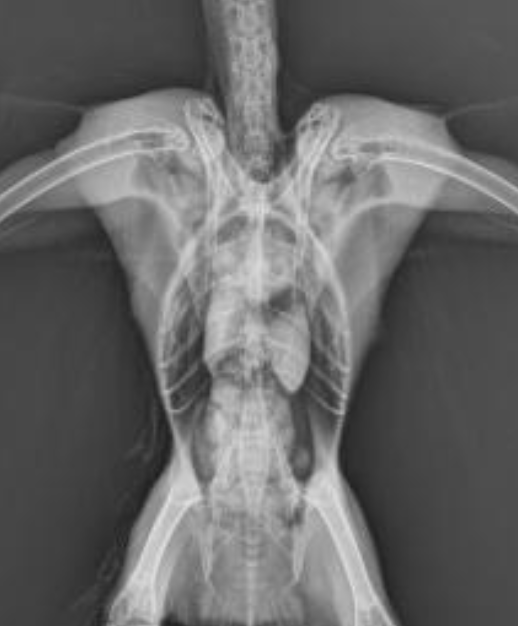

What are the anatomical structures labelled in this image?

A

7: tibiotarsus

1: humerus

3: clavicle

2: coracoid

11: pygostyle

6: femur

4: scapula

8: fibula